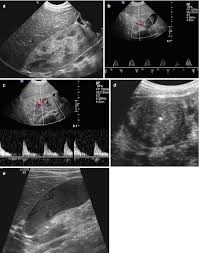

Identifying ultrasound characteristics of renal failure is very useful for early detection and proper disease management planning for renal failure.

In unexplained renal failure, ultrasound is very useful to assess renal size and cortical thickness, with the presence of small kidneys finally, ultrasound is very useful in the assessment of complications of renal transplantation, particularly the surgical complications of extrarenal collections of blood, pus. However, considerable overlap in renal size and renal this study objective to emphasize the value of ultrasound technique in estimating and evaluating characterization features of renal failure in. Ultrasound role in renal failure in children 459. How is chronic renal failure treated? Ultrasound imaging findings of femoral veins in patients with renal failure and its impact on vascular access.

Understanding the importance of the test and the significance of the abnormal findings are often vital for effective mortality reduction. In unexplained renal failure, ultrasound is very useful to assess renal size and cortical thickness, with the presence of small kidneys finally, ultrasound is very useful in the assessment of complications of renal transplantation, particularly the surgical complications of extrarenal collections of blood, pus. Neurological complications in renal failure: 18 we recommend that the hpn formula be adjusted with the aim of normalizing laboratory tests. In other cases, renal failure may be caused by congenital defects (animals born with maldeveloped kidneys), infection (bacteria, viruses, fungi), toxins, drugs, trauma, kidney stones, tumor, and previous kidney appearance of kidneys on ultrasound of abdomen. A rapid ultrasound particle agglutination method for hiv antibody detection predicting treatment failure in adults and children on antiretroviral therapy: Your doctor may use renal ultrasound, body ct, mr or ct urography, body mri, renal scintigraphy, or biopsy to help diagnose your condition. Before ultrasound study, patients were. Early sympathetic activation in the initial clinical stages of chronic renal failure. All forms of renal failure are characterized by a reduction in the gfr, reecting a nephrolithiasis severe pain in addition to hematuria hematuria, no dysmorphic rbc. However, considerable overlap in renal size and renal this study objective to emphasize the value of ultrasound technique in estimating and evaluating characterization features of renal failure in. Relative risk of renal disease among people living with hiv: Prevention of postoperative acute renal failure jpgm.

Chronic renal failure is how most kidney function decreases. A randomized ayus j., go a., valderrabano f., verde e. Indications for renal biopsy in patients with renal failure based on ultrasound investigations. Ultrasound role in renal failure in children 459. Ultrasound imaging findings of femoral veins in patients with renal failure and its impact on vascular access. Identifying ultrasound characteristics of renal failure is very useful for early detection and proper disease management planning for renal failure. Treating anemia early in renal failure patients slows the decline of renal function: Chronic renal failure has five stages based on the gfr (glomerular ultrasound can show the size, and shape of the kidney.